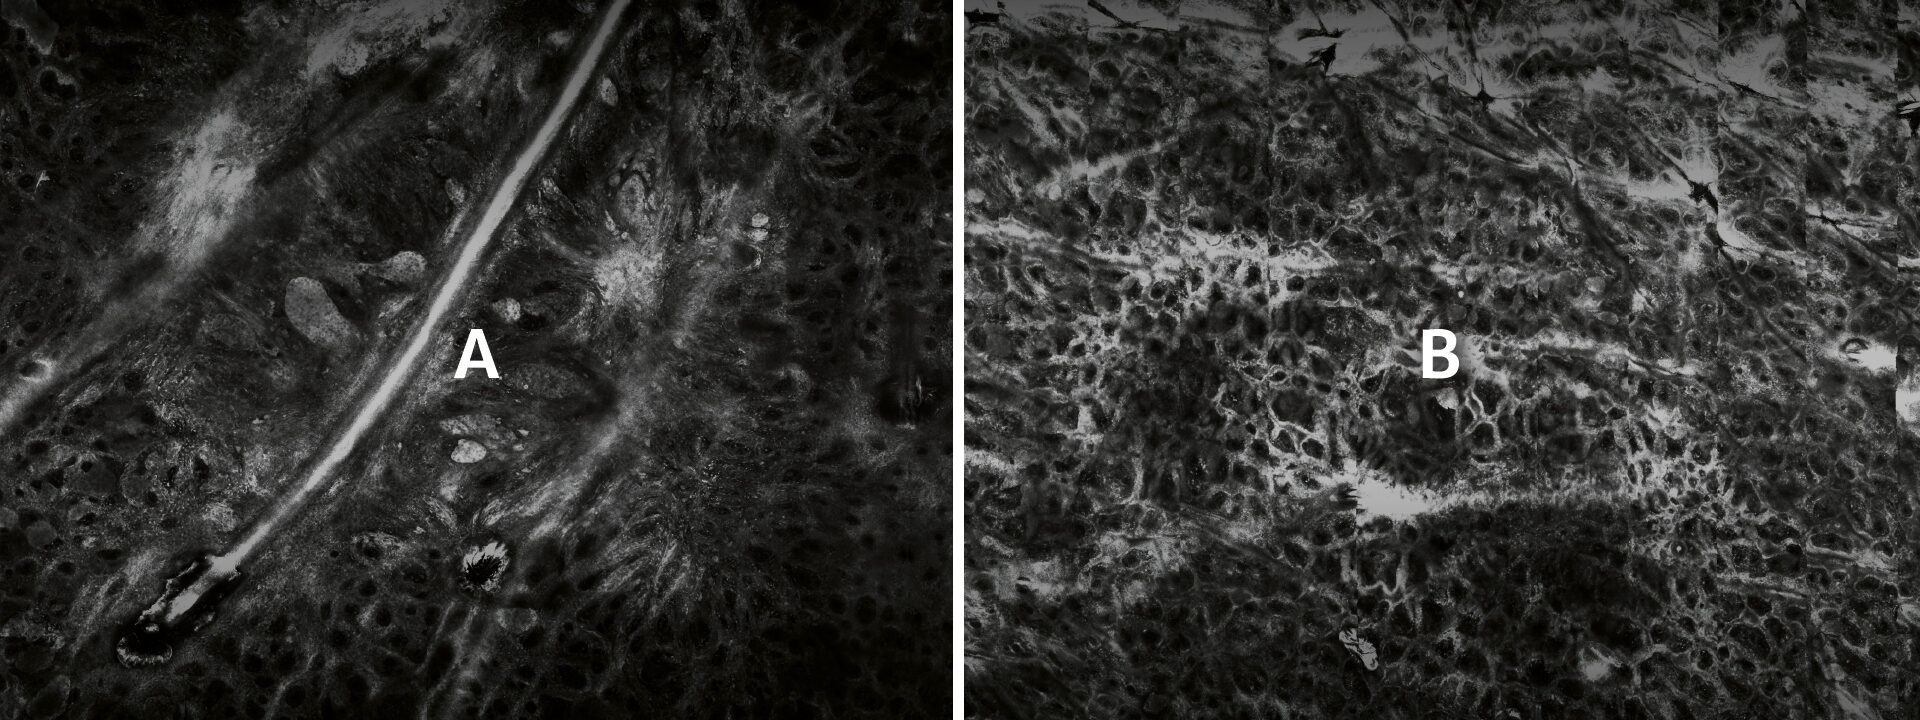

The VivaScope technology (in vivo) allows for a real-time and non-invasive Instant Optical Biopsy from the epidermis to the upper dermis. With the VivaScope confocal laser scanning microscopy (CLSM) the cell morphology of the skin layers are displayed in high resolution.

In vivo examinations with the VivaScope technology using confocal laser scanning microscopy (CLSM) allow for an optical biopsy using a non-invasive procedure. Cellular microstructures of skin can thereby be depicted cell by cell in clearly defined horizontal “optical cross-sections” with a thickness of less than 5.0 μm.

Can you identify the melanoma?

In Vivo examinations using confocal laser scanning microscopy (CLSM) allow for an optical biopsy and noninvasive procedure. Cellular microstructures of skin

can thereby be depicted cell by cell in clearly defined horizontal “optical cross-sections” with a thickness of less than 5.0 μm.